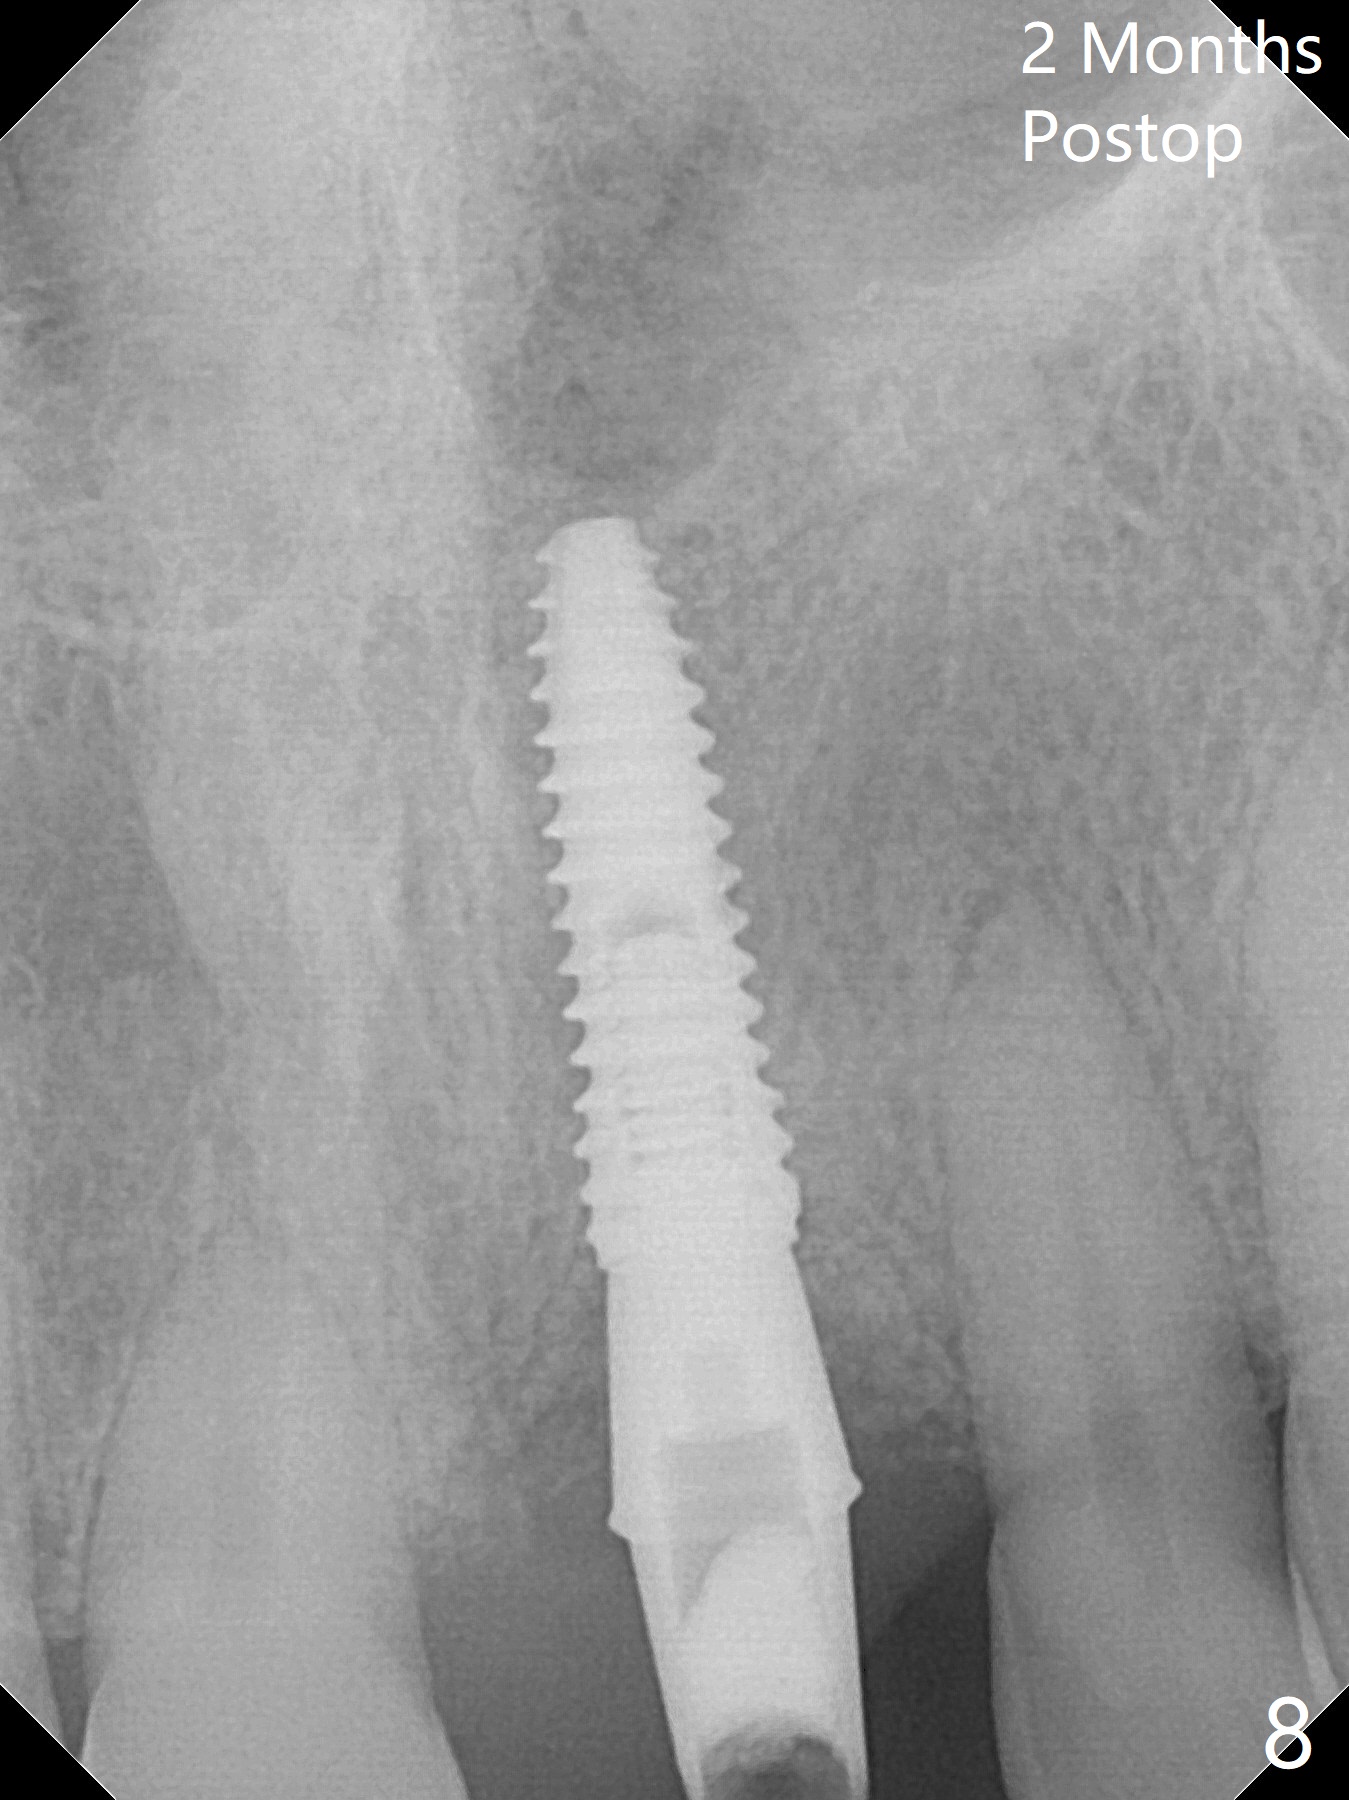

Preop examination shows mobility I of the teeth #8 and 10 and apparent occlusal trauma from #22-26 implant bridge. After occlusal equilibrium, incision reveals low, but moderate ridge at #9 (Fig.1). Fig.2a is a cross section of a normal upper incisor socket with thin buccal plate (B) and thick palatal one (P). It is difficult to initiate osteotomy in the oblique palatal wall when the buccal plate is resorbed (Fig.2b). In this case with horizontal buccal and palatal plate bone loss, the socket bottom is flat (Fig.2c), easy for osteotomy (Fig.2d green arrow, Fig.3). The initial osteotomy deviates mesial (Fig.3). To avoid perforation into the Incisive Canal, the trajectory is changed (Fig.4). After use of the final drill (3 mm), the coronal Incisive Canal is perforated. Following placement of a 3.5x13 mm implant and 4.5x5.5(4) mm abutment, Vanilla Graft is placed (Fig.5 *) to repair the perforation. Retrospectively, the coronal end of the Incisive Canal is revealed at incision (Fig.1 *). The initial osteotomy should be slightly more distal (Fig.3 black line). The buccal plate looks bulky due to placement of the abutment and bone graft 1 week postop (Fig.6,7 (crown dislodgement)). The bone graft appears to remain in place 2 months postop (Fig.8). Impression is taken because of instability of the immediate provisional (Fig.9 after Laser gingivectomy). The gingiva and buccal plate remain healthy 4.5 months postop (Fig.10). A permanent crown is cemented (Fig.11).